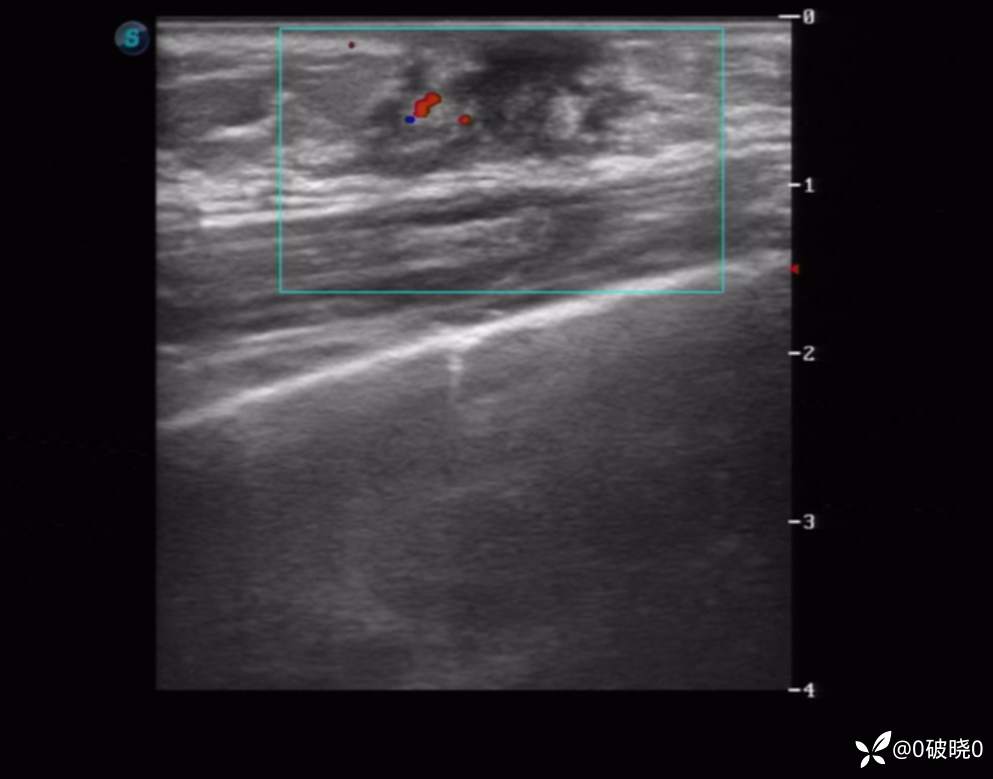

女童,7岁,9天前突感乳头处疼痛,当时家长触及到花生米大小的结节,9日后发现结节长大至2cm,但疼痛减弱,遂来诊。超声显示:包块处呈腺体样回声,其内回声不均,可见不规则低回声及团样高回声区,其旁可见细管样回声。CDFI:其内可见点、条状动脉血流信号。